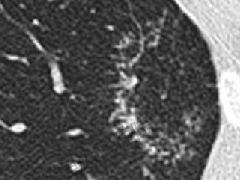

肺段与肺内管道应用解剖  肺转移瘤的十种不典型CT表现

肺转移瘤的十种不典型CT表现  肺内淋巴结的CT表现特点及与病理对照

肺内淋巴结的CT表现特点及与病理对照  肺实变与肺不张的CT鉴别诊断